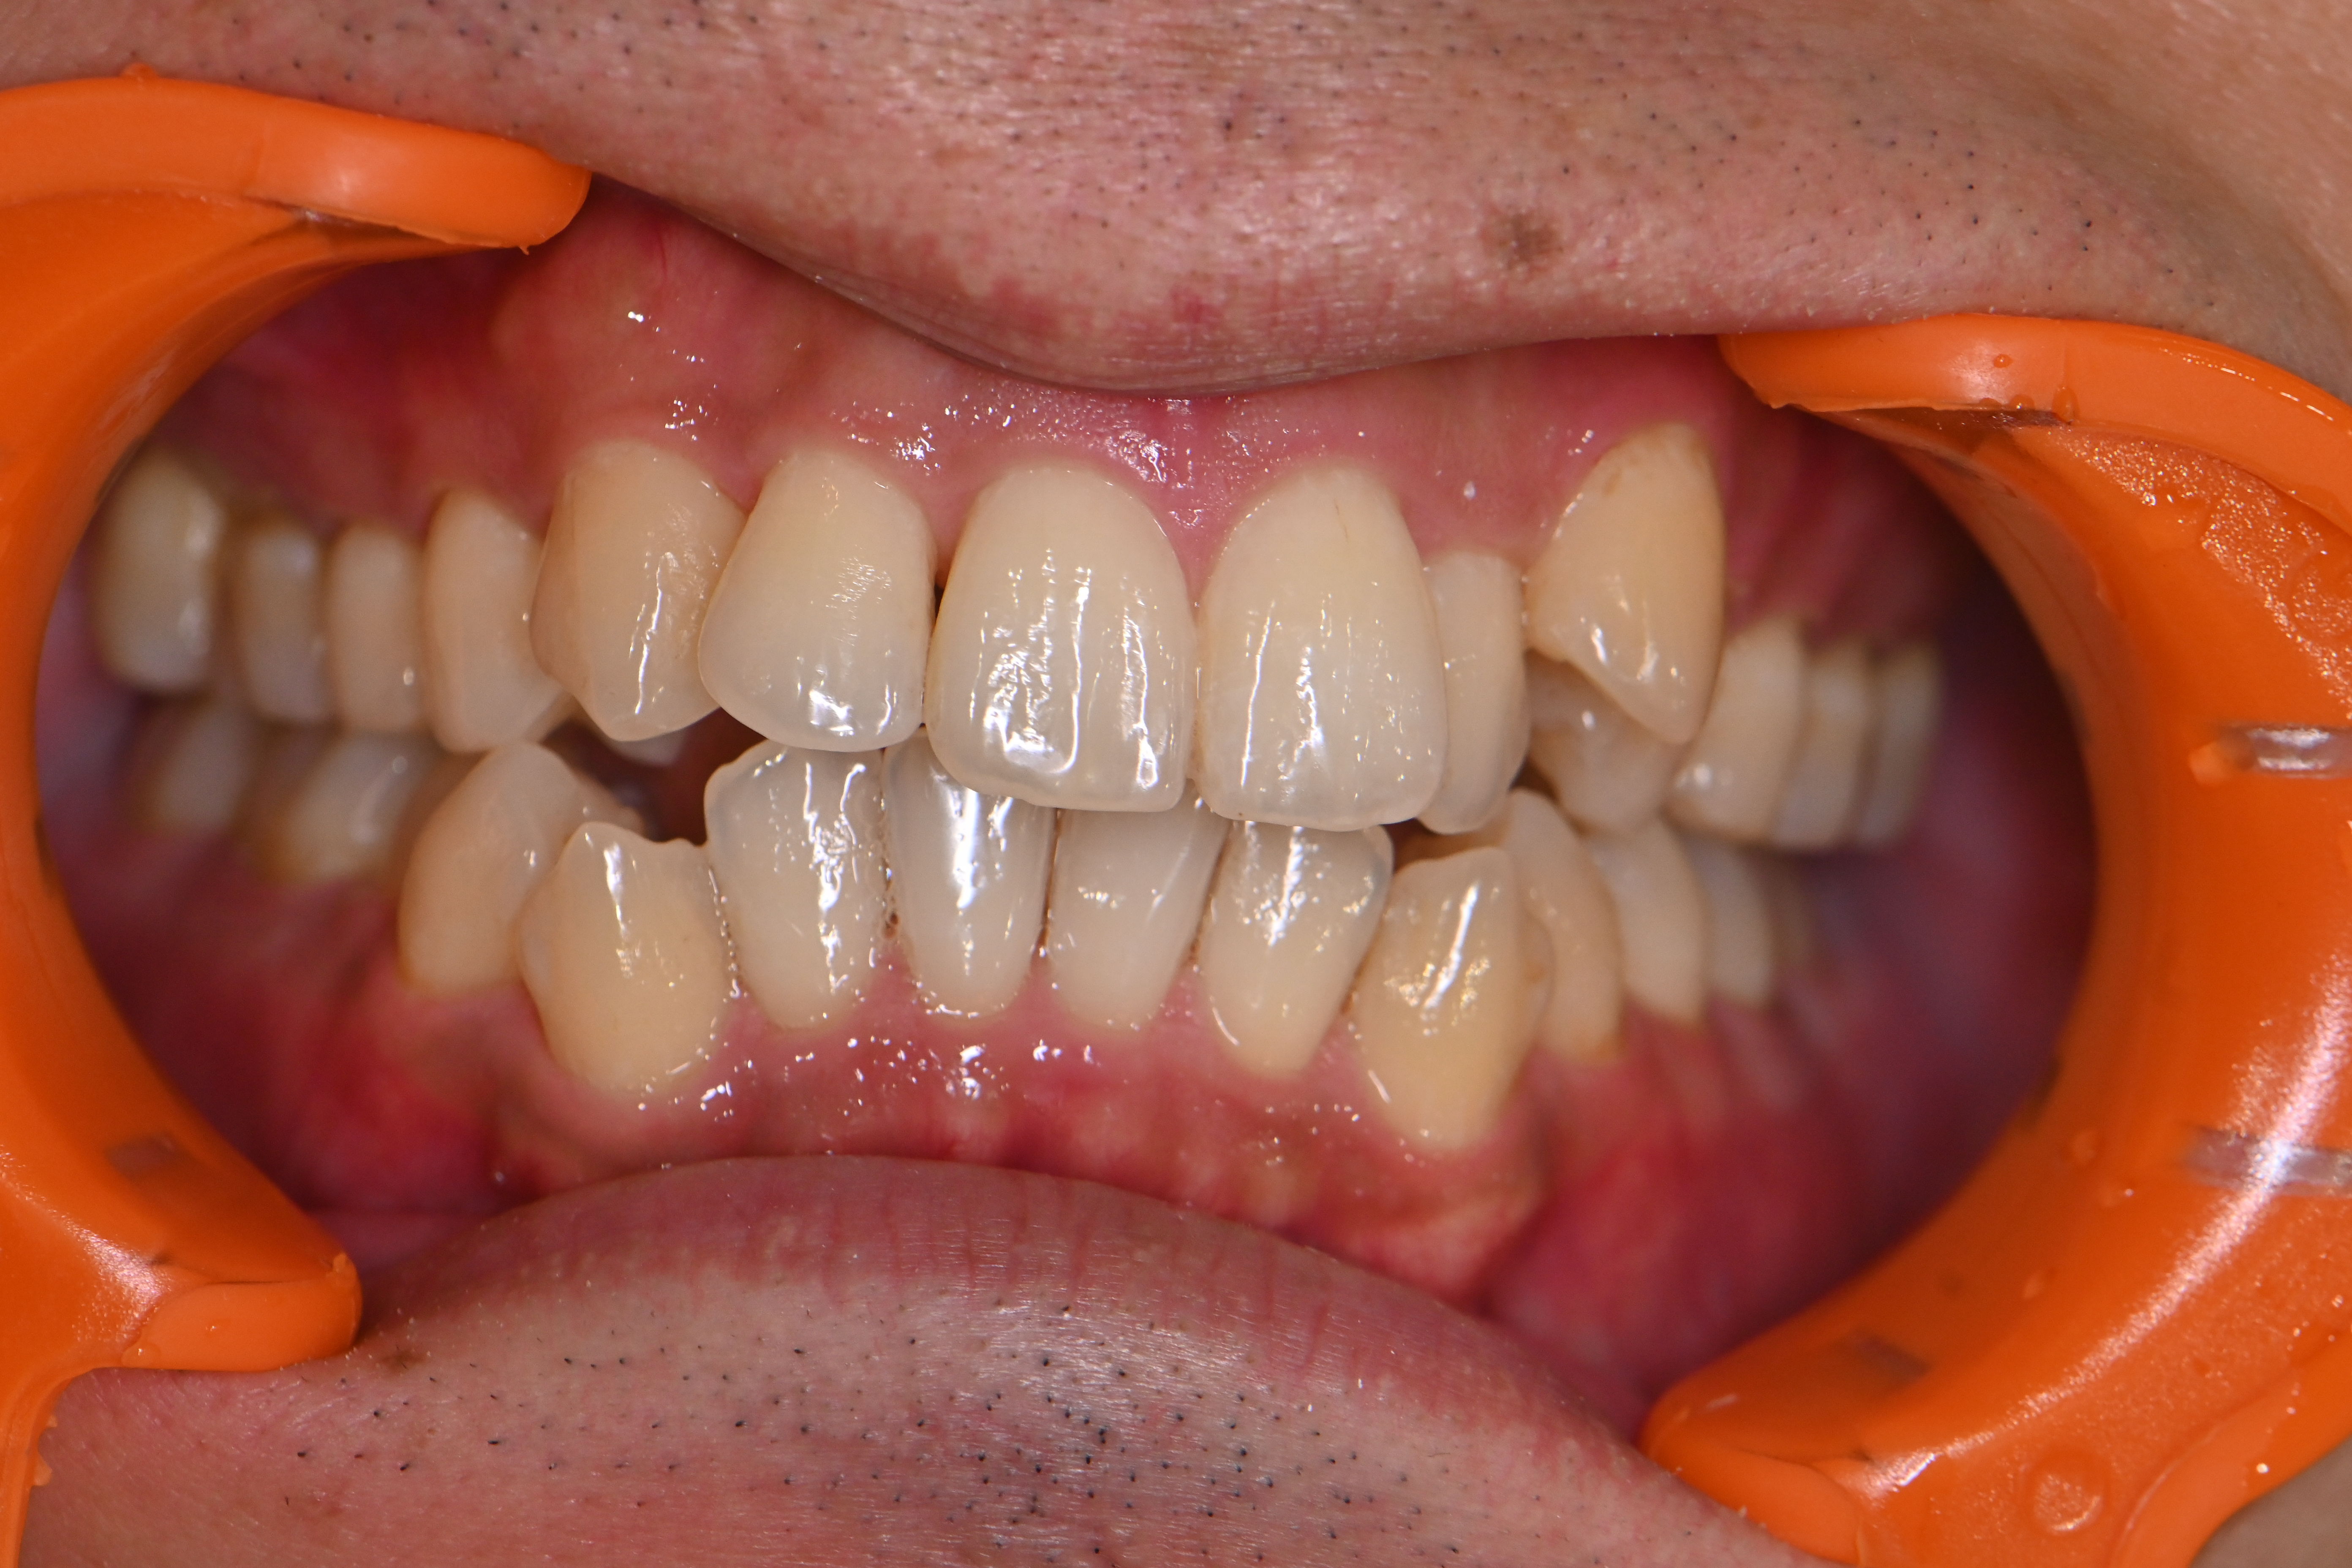

細かい着色をエアフローでしっかり除去して、仕上げにリナメル(歯の細かい傷を埋めてくれる)を塗布しました✨

どのくらいで再度着色が付いてしまうのか経過を追って適切なタイミングで再度エアフローを提案しようと思います!

○処置内容…歯科衛生士処置60分(エアフロー)

○費用…¥11,000

○担当…DH高橋